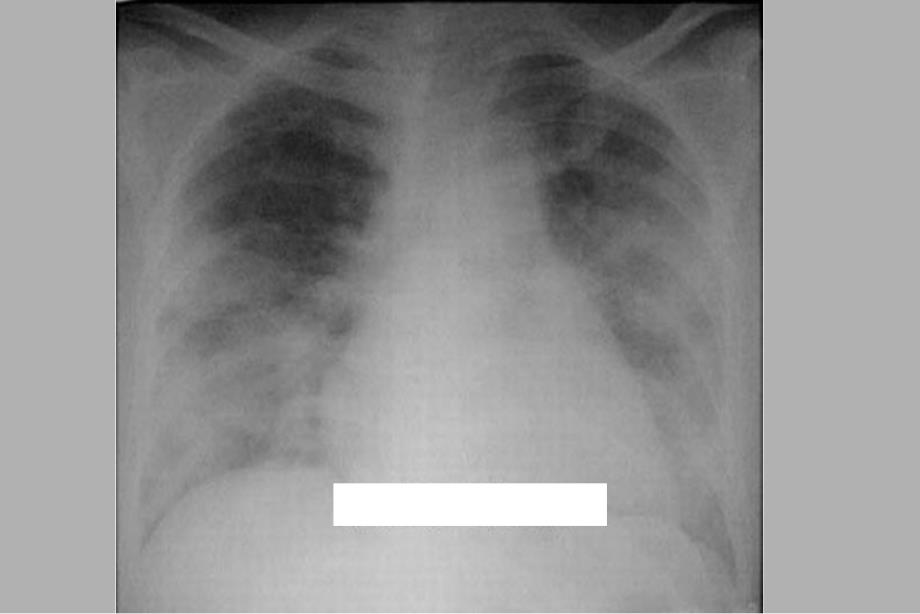

1、呼吸机所致肺损伤与呼吸机所致肺损伤与肺保护性通气策略肺保护性通气策略急性肺损伤急性肺损伤/急性呼吸窘迫综合征急性呼吸窘迫综合征(ALI/ARDS)非心源性肺水肿,肺泡大量萎陷非心源性肺水肿,肺泡大量萎陷 严重肺内严重肺内分流及通气分流及通气/血流比例失调,血流比例失调,临床表现为不易临床表现为不易缓解的急性进行性缺氧性呼吸衰竭缓解的急性进行性缺氧性呼吸衰竭 能有效通气的肺泡减少,病变不均匀能有效通气的肺泡减少,病变不均匀 容易容易发生呼吸机相关肺损伤发生呼吸机相关肺损伤呼吸机所致肺损伤(呼吸机所致肺损伤(VILI)的概念)的概念 肺气压伤(肺气压伤(barotrauma)肺容积伤(肺容积伤(v

3、变 肺实质病变的不均一性肺实质病变的不均一性 通气量的大小通气量的大小 峰压切换过大峰压切换过大 平均肺泡压过高平均肺泡压过高 通气频率通气频率 通气的时间通气的时间 分泌物滞留分泌物滞留VILIVILI的诊断的诊断 警惕:认识高危因素警惕:认识高危因素 尤其在人尤其在人-机协调较差时机协调较差时 查体查体 X X-线征象线征象 标记物标记物肺保护性肺保护性 通气策略通气策略 避免潮气量过大:小潮气量通气避免潮气量过大:小潮气量通气(限压限压)避免终末气道的反复开闭:避免终末气道的反复开闭:PEEPPEEP的应用的应用CT scan at 0 cmH2O PEEP(A),and at 15 c